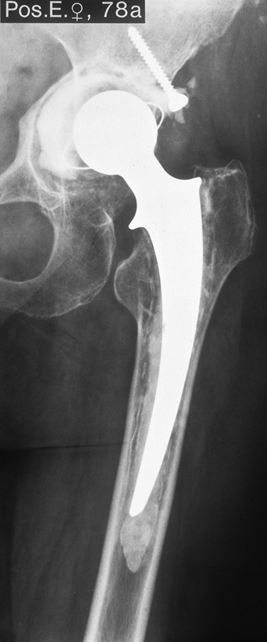

Fallbeispiel

Weiblich, 78 Jahre. Die

Bilder zeigen eine deutlich gelockerte zementierte

Hüftprothese. Der Knochen um den Zement ist stellenweiße

papierdünn

Zustand nach Austausch der

zementierten Prothese durch eine Bicon-Pfanne sowie

einen SLR-Schaft.

Die Röntgenbilder zeigen das Ergebniss nach 13 Jahren.

Die nun 91 jährige Patientin ist gut gehfähig und völlig

beschwerdefrei.